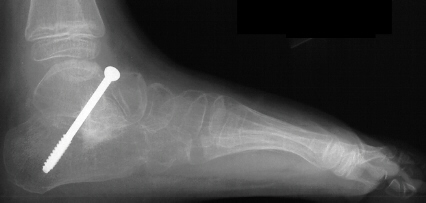

of the left foot. The procedure consisted of :

- subtalar arthrodesis with autograft bone graft and screw fixation

- closing wedge calcaneocuboid arthrodesis with open pinning

- reduction and open pinning of the talonavicular joint

- midfoot soft tissue release of the talonavicular, calcaneocuboid and

subtalar joints

Post operatively, the patient was placed in a long leg cast. Preliminary

results show satisfactory reduction of the talonavicular joint, correction

of hindfoot valgus, dorsiflexion of the talus on the calcaneus, and correction

of forefoot adduction immediately post op.